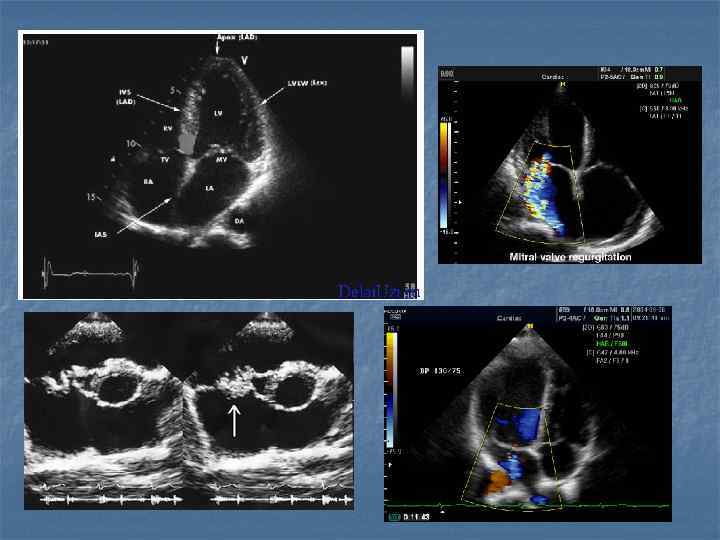

Показания n n n n Воспалительные заболевания брюшной полости, малого таза и шеи… Наличие жидкости в брюшной и грудной полостях, в суставах Визуализация мягких тканей(мышцы, связки, околосуставные пространства) Желчекаменная, почечнокаменная болезни Диагностика опухолей (молочная железа, яичники, лимфоузлы) Заболевания сосудов(варикозная болезнь, эндортереит, оартиты, аневризмы, ангиопатия) Врожденные и воспалительные заболевания сердца(пороки клапанного аппарата, дефекты стенок, нарушение функции миокарда, эндокардит, перикардит)